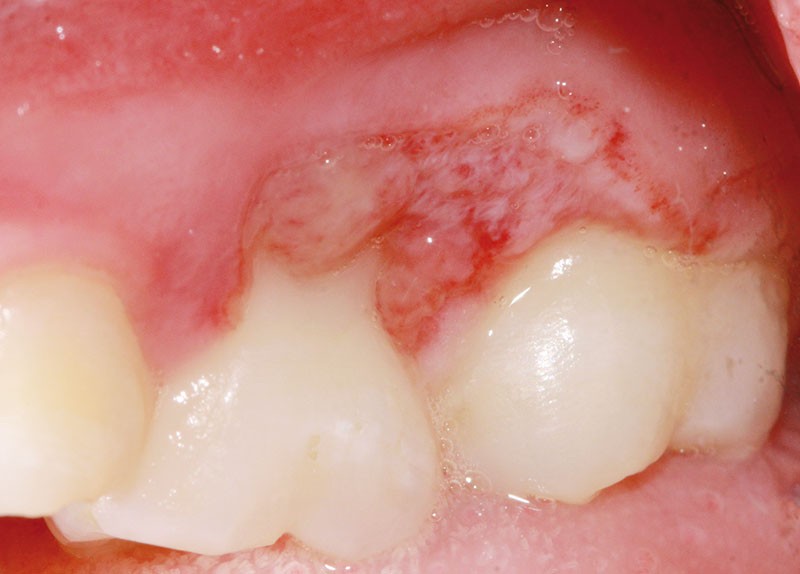

L’examen clinique révèle la présence d’une ulcération végétante, d’environ 1 cm de diamètre, localisée sur les gencives marginale, papillaire et attachée en vestibulaire de 55 et 16, associée à une récession parodontale pour 55. L’ulcération est bien délimitée, indolore et non hémorragique spontanément. Les dents présentent une mobilité physiologique et il n’existe pas d’adénopathie.

L’hypothèse la plus probable est celle d’une blessure d’origine traumatique, même si la jeune patiente et son entourage n’ont aucun souvenir des circonstances d’apparition.

L’origine systémique ou tumorale de l’ulcération est écartée dans un premier temps, étant donné l’absence de signes généraux et la fréquence particulièrement rare des carcinomes épidermoïdes chez les enfants.

Lors du contrôle à une semaine, la situation clinique ne s’est pas améliorée et devant l’aspect…